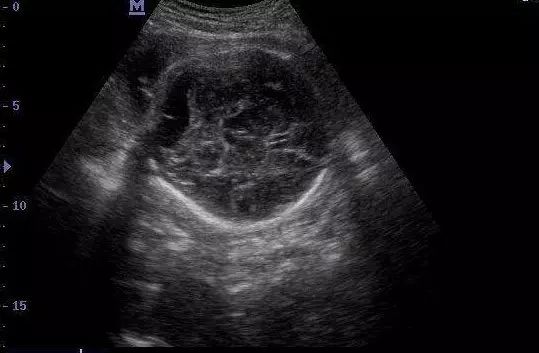

文静是位比较开朗的孕妈,拿了好几张孕期B超检查单请我看,一张是孕26周时做的B超,提示胎儿双侧脑室后角宽8.2mm,一张是孕28周复查时显示宽7.2mm,还有一张是孕32周显示:胎儿后颅窝池宽约9.2mm,右侧侧脑室后角宽约8.3mm。文静紧张得不得了,担心宝宝会有脑积水,请我一定给诊断和解释一下。

通常从孕20周开始,常规做胎儿超声检查时,系统观察胎儿颅内侧脑室和颅后窝部位,一般来说,胎儿侧脑室后角及后颅窝池的宽度(积水 )在10mm以内者,多为正常变异,在10-14mm以内者,如果不合并颅内外畸形和染色体异常,一般不会造成严重不良的后果,而双侧、多部位、最大积液量≥15mm的胎儿,合并颅内外畸形及染色体异常明显增高,就最危险,尤其是多部位积液的患儿。

先天型脑积水的胎儿,一旦合并颅内外畸形和染色体异常,则易造成各种后遗症。如先天愚型等,但轻度为单纯性脑积水的胎儿,颅内积液可自行消失或出生后经治疗可改善。因此发现胎儿颅脑积液,不要轻率地做出结论,应结合胎儿的孕龄、积液量的变化,积液的部位范围,是否伴有胎儿染色体异常或颅内外畸形,以及胎儿大小等因素综合考虑,判断胎儿脑积水的后果,最后作出处理决定。积液量10mm胎儿,定期随访积液逐渐减少、消失或无变化,考虑为正常变异,对宝宝以后没有明显影响,可以继续妊娠,对积液在10-14mm的胎儿,应先排除有无合并畸形和染色体异常,若无,则可以继续妊娠,并每2周做一次B超复查,观察积液量的变化,如积液量增多或出现多部位积液,应视为病变发展,反之则视为好转。对积液≥15mm的胎儿,并伴有颅内多部位积液者,若达到高峰孕周,孕29-32周后仍明显消退,必须高度重视,做染色体检查,一旦判断后遗症可能极大,应尽快引产。